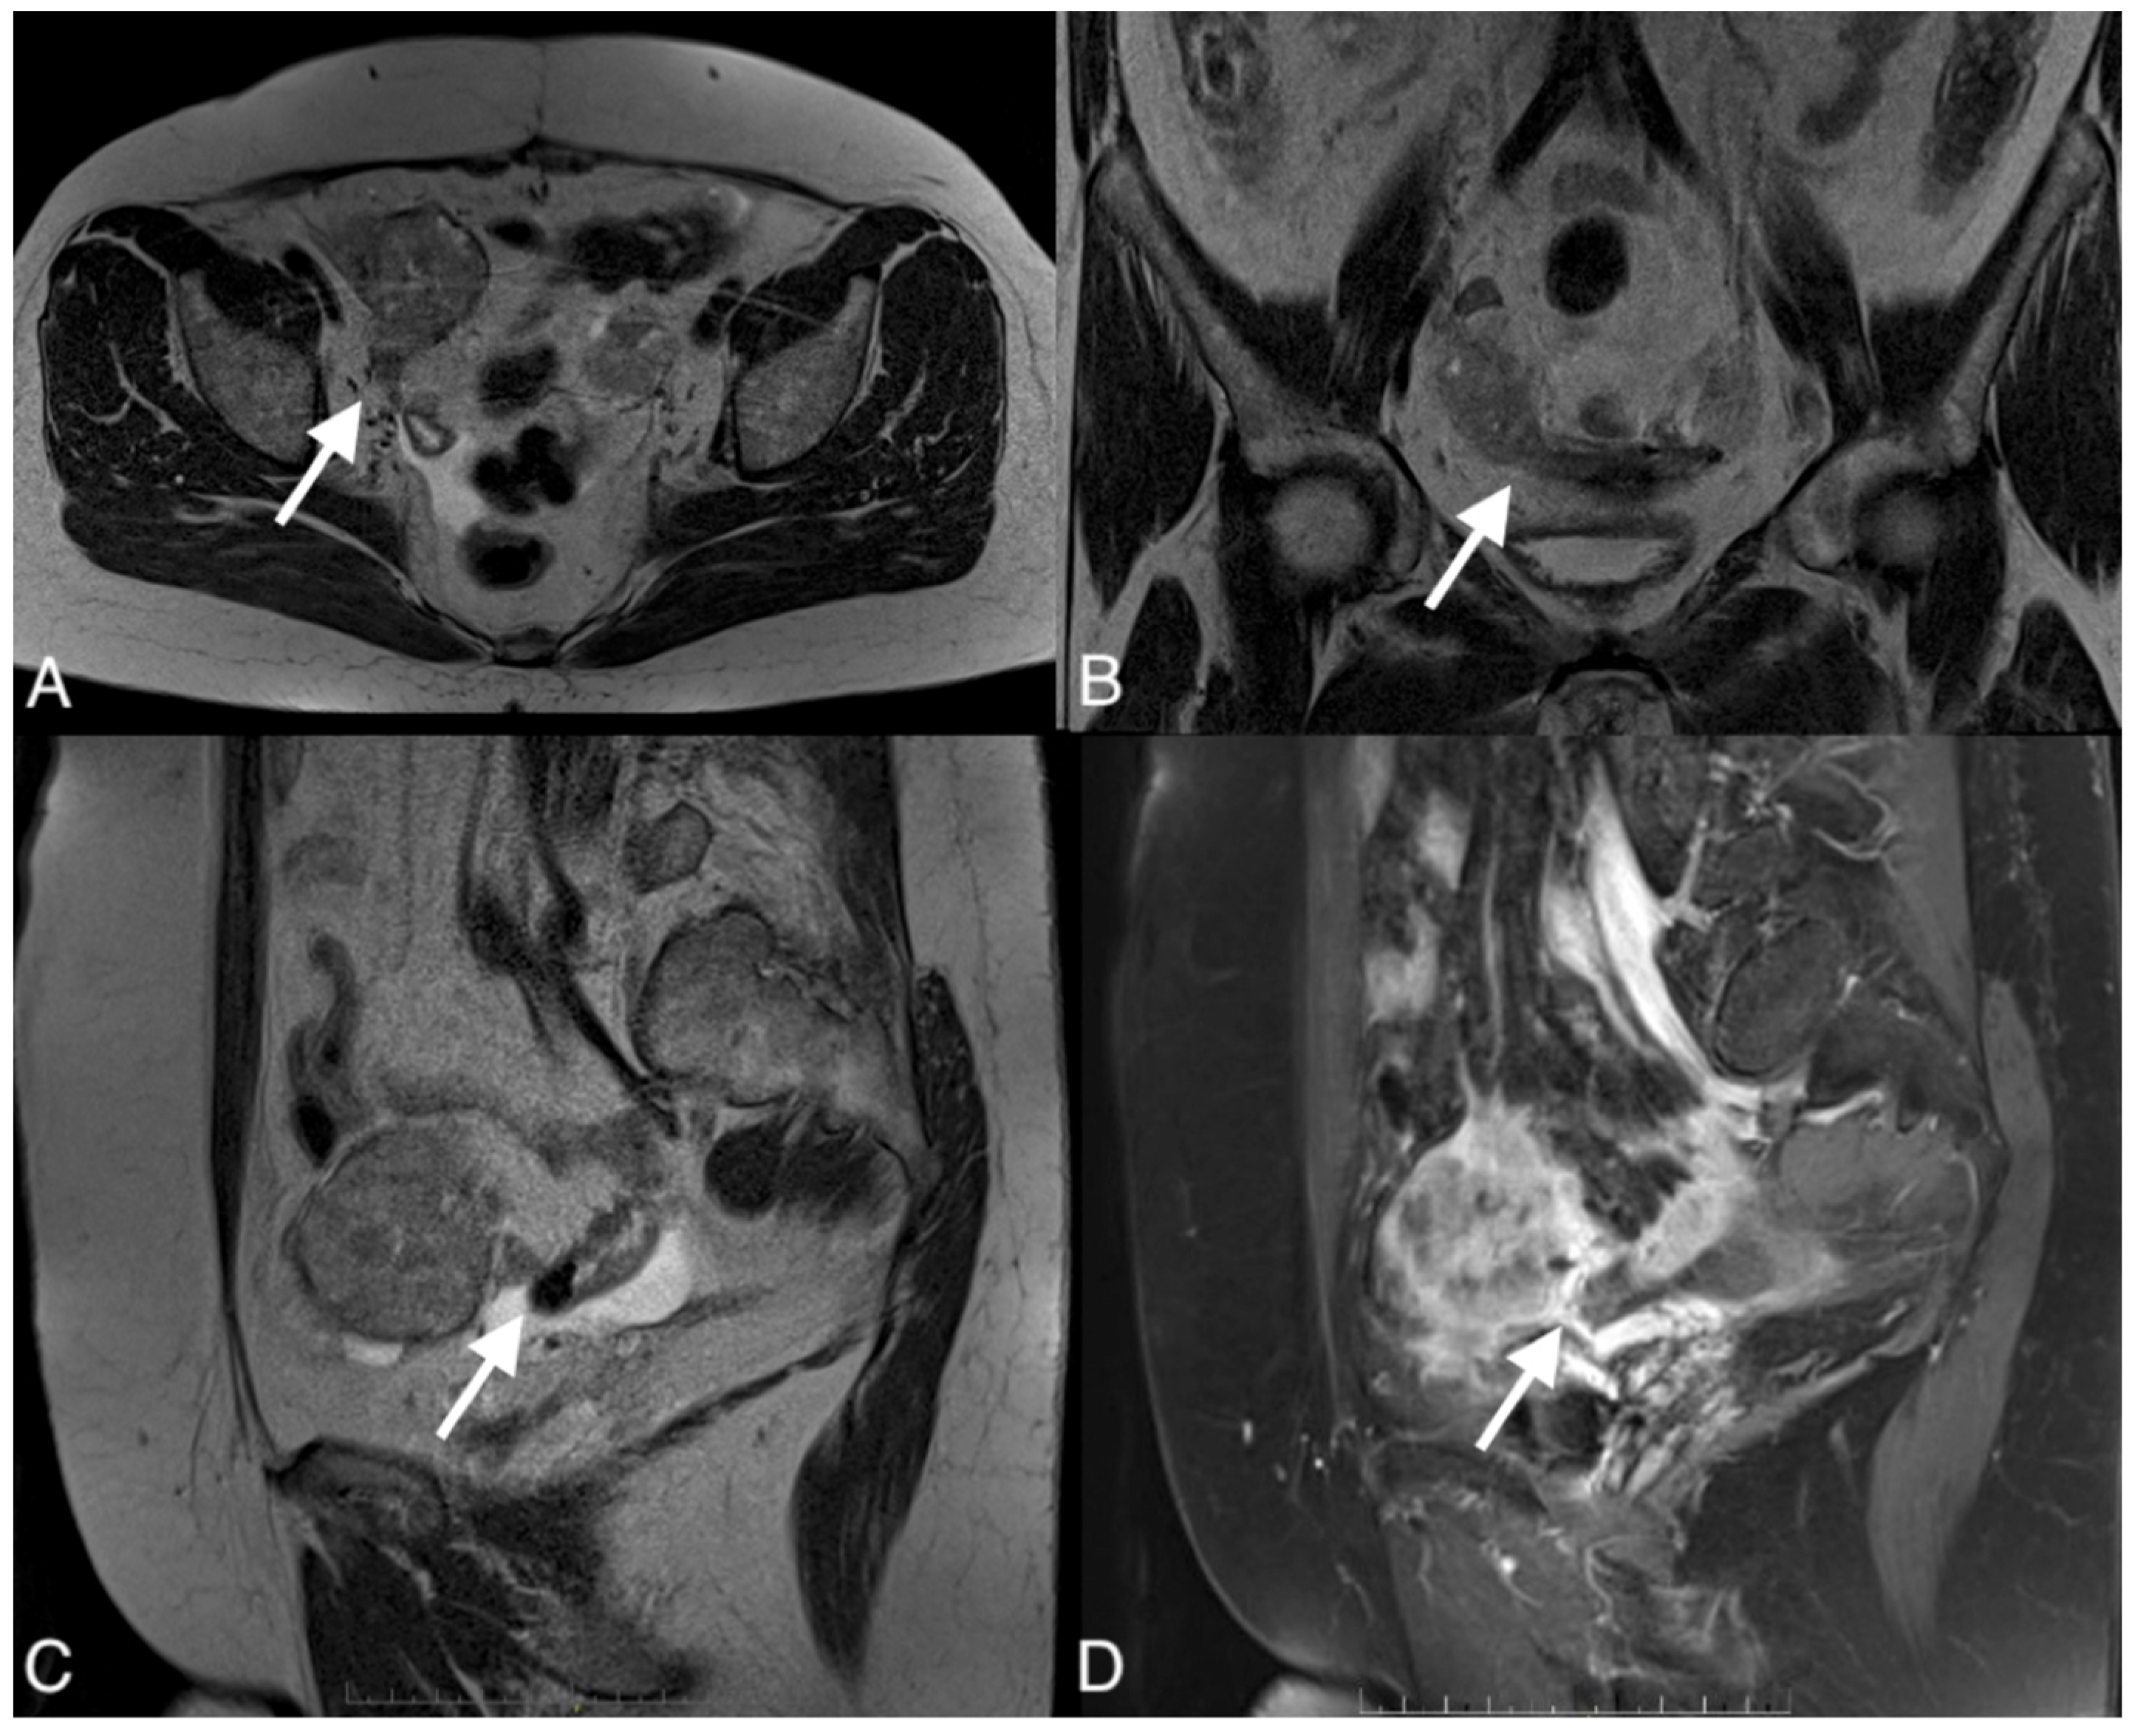

Figure 5.

Images of a 67-year-old woman with a recurrent high grade serous ovarian cancer. MRI T1-weighted post-contrast image obtained in the axial plane (A), coronal plane (B), sagital plane (C), and T1-weighted image post-contrast (D) show large pelvic tumor and fistula (arrows) between the tumor and sigmoid colon.

To confirm the suspected fistula, the patients were referred for MRI. In all cases, the fistula was visible on the MR images, showing hypointensity on the T2 and T1 post-contrast sequences but no restricted diffusion on the DWI sequence. The fistula in one of the patients was hyperintense on T2 images and hypointense on T1-weighted images and showed restricted diffusion on DWI.

Interobserver agreement was 75% for CT and 87.5% for MRI, corresponding to a high level of agreement (Figure 4 and Figure 5).